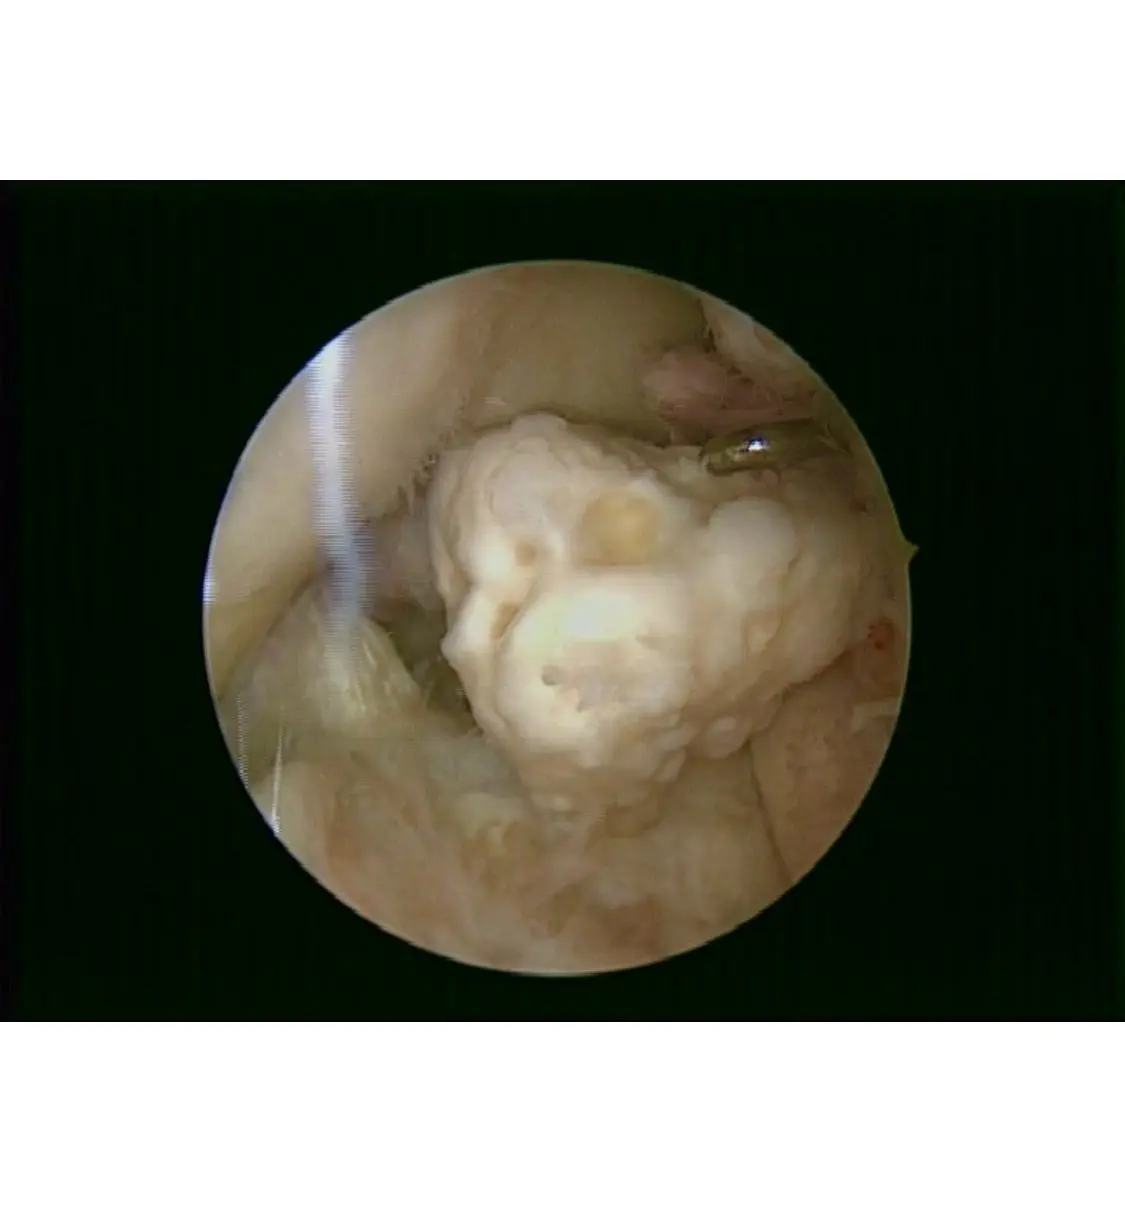

Planificación 3D

Escaneo y mapeo de tu rodilla para definir cortes milimétricos y elegir el implante ideal.

Incisiones precisas, mínimo trauma y balance ligamentario optimizado con el brazo robótico.

Galería de fotos